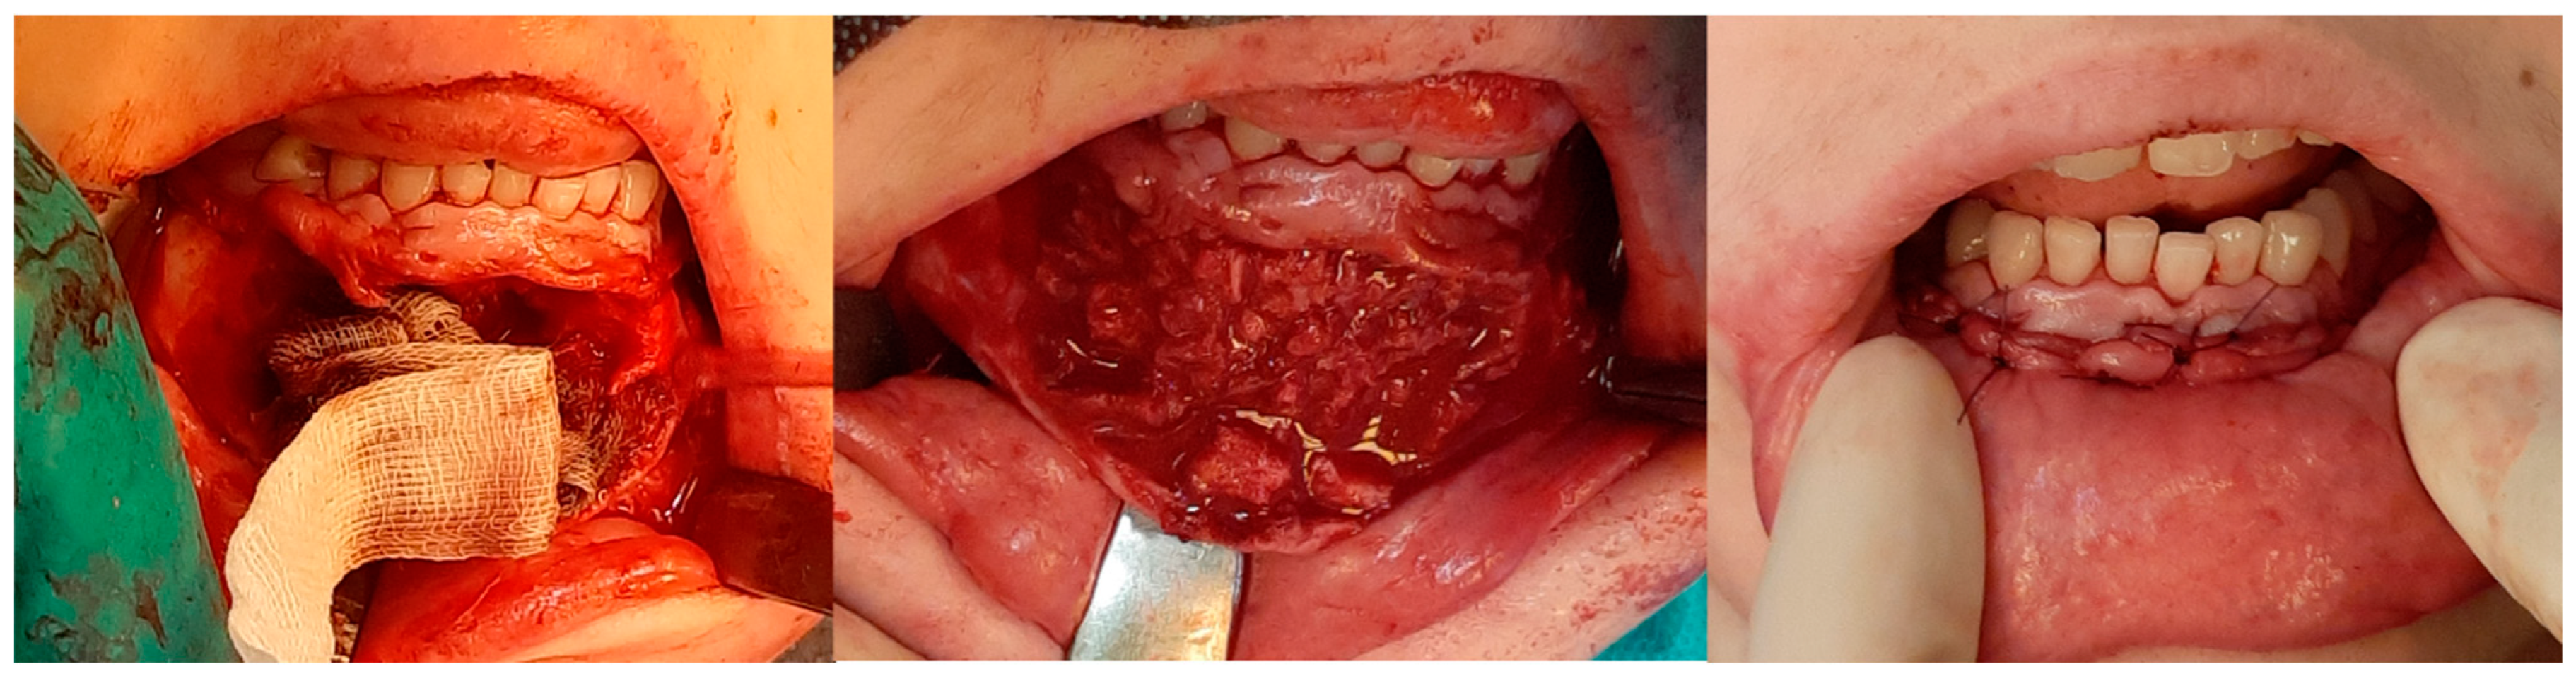

3. Results

3.2. Injections

4. Discussion